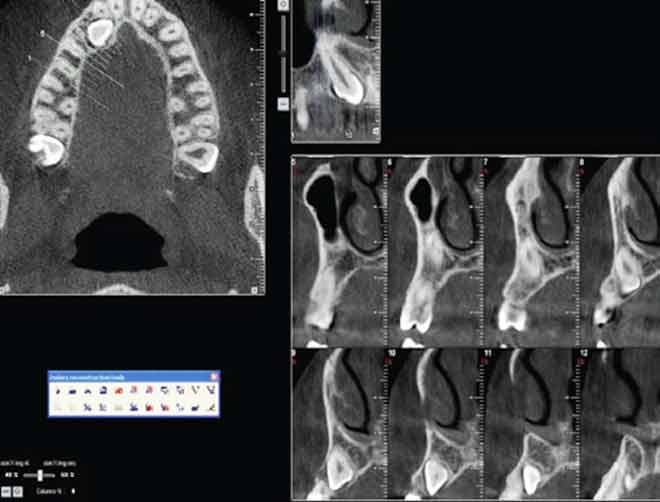

Fig 7 : Coupes sagittales montrant des articulation temporo-mandibulaire |